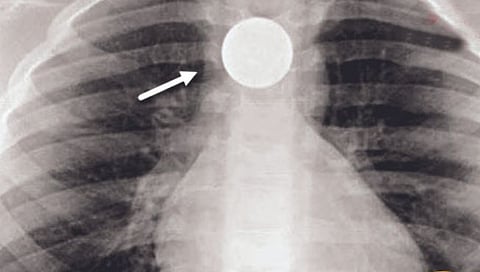

इंदूर ः लहान मुलं कधी काय उपद्व्याप करतील हे सांगता येत नाही. तोंडात पेन्सिल, नाणी घालणारे अनेक मुले असतात. मध्य प्रदेशात इंदूरमध्ये नुकतेच 21 वर्षांची एक तरुणी हॉस्पिटलमध्ये तपासणीसाठी गेली असताना तिच्या अन्ननलिकेत एक रुपयाचे नाणे अडकल्याचे दिसून आले. हे नाणे ती आठ वर्षांची असताना तिने गिळले होते. त्यानंतर आता तेरा वर्षांनी हे नाणे बाहेर काढण्यात आले!

या तरुणीचे नाव नाजमीन. तिचे वडील फारुख यांनी सांगितले की ते इंदूरमध्ये राहतात आणि मजुरी करतात. त्यांची कन्या नाजमीन आठ वर्षांची असताना तिने हट्ट केल्याने चॉकलेट खरेदी करण्यासाठी तिला एक रुपयाचे नाणे दिले होते. त्यावेळी तिने हे नाणे तोंडात ठेवले आणि गिळले. ते तिच्या अन्ननलिकेत अडकले होते. तिने काही वेळा उलट्या केला आणि नंतर ती बरी झाल्याचे दिसले. त्यानंतर तेरा वर्षे या गोष्टीकडे कुणाचे लक्ष गेले नाही व तिलाही कसला त्रास जाणवला नाही. मात्र, अलीकडे तिचे वजन सातत्याने कमी होत होते. तपासणीवेळी दिसून आले की हे नाणे अद्याप तिच्या अन्ननलिकेत अडकून राहिलेले आहे. डॉक्टरांनी शस्त्रक्रिया करून हे नाणे बाहेर काढले.